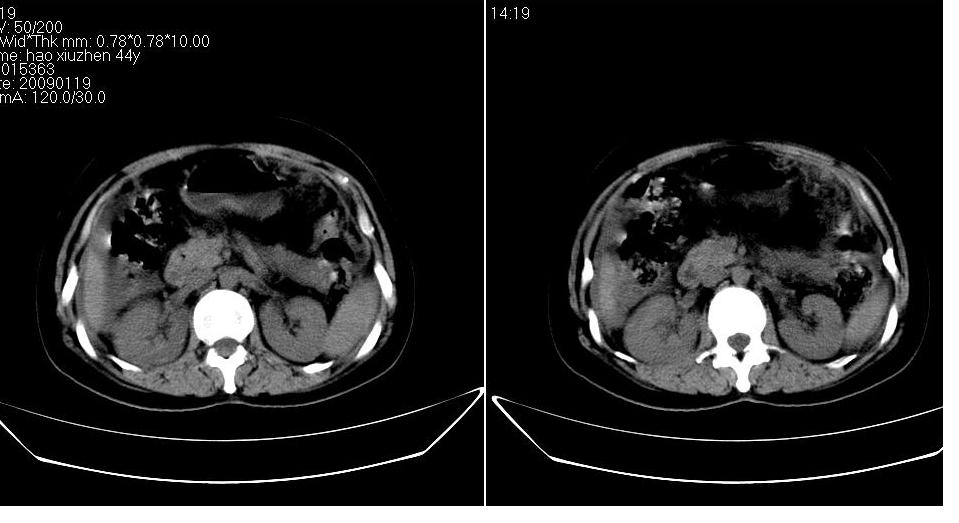

以下是引用zbp537在2009-1-19 14:09:00的发言:[br]从这个平扫图像上看,只能考虑:1、胸腹水。2、脾脏包膜下弧形高密度影,疑出血,建议复查。[br]既然腹水中有恶性细胞,建议行腹部ct增强扫描及胸部扫描。

以下是引用随光逐影在2009-1-19 15:47:00的发言:[br]1)不排除胃癌可能;建议行胃镜检查。2)腹水。3)右侧胸腔积液。

以下是引用jiangjing在2009-1-19 18:21:00的发言:[br]1 网膜污垢征---肿瘤网膜转移.2)腹水。3)右侧胸腔积液